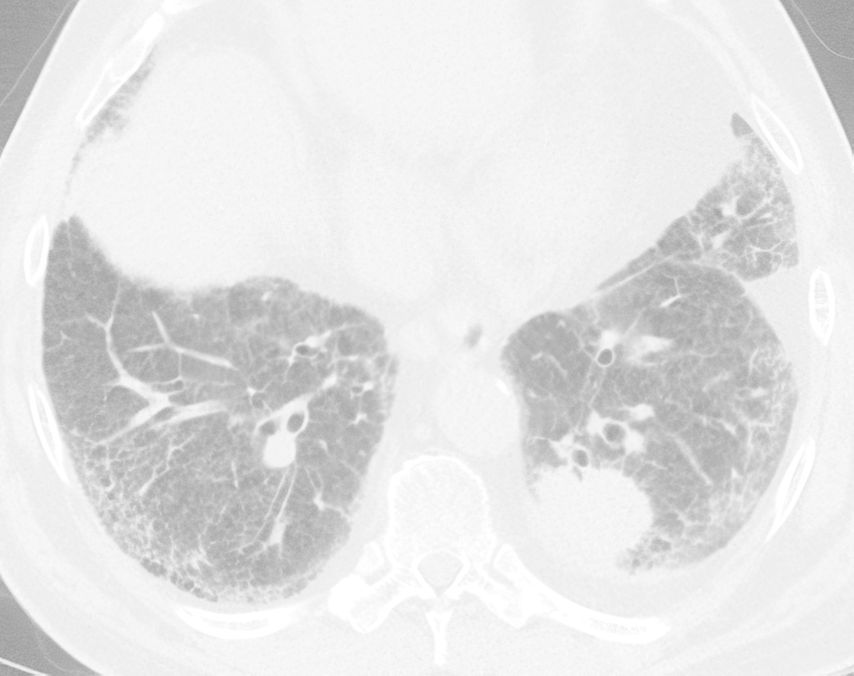

Abb. 1: Fallbeispiel: CT-Aufnahme mit neu aufgetretenem pulmonalem Plattenepithelkarzinom li. bei vorbekannter idiopathischer Lungenfibrose mit UIP-Muster, re. subpleural gut sichtbare Honigwabenzysten („honeycombing“)